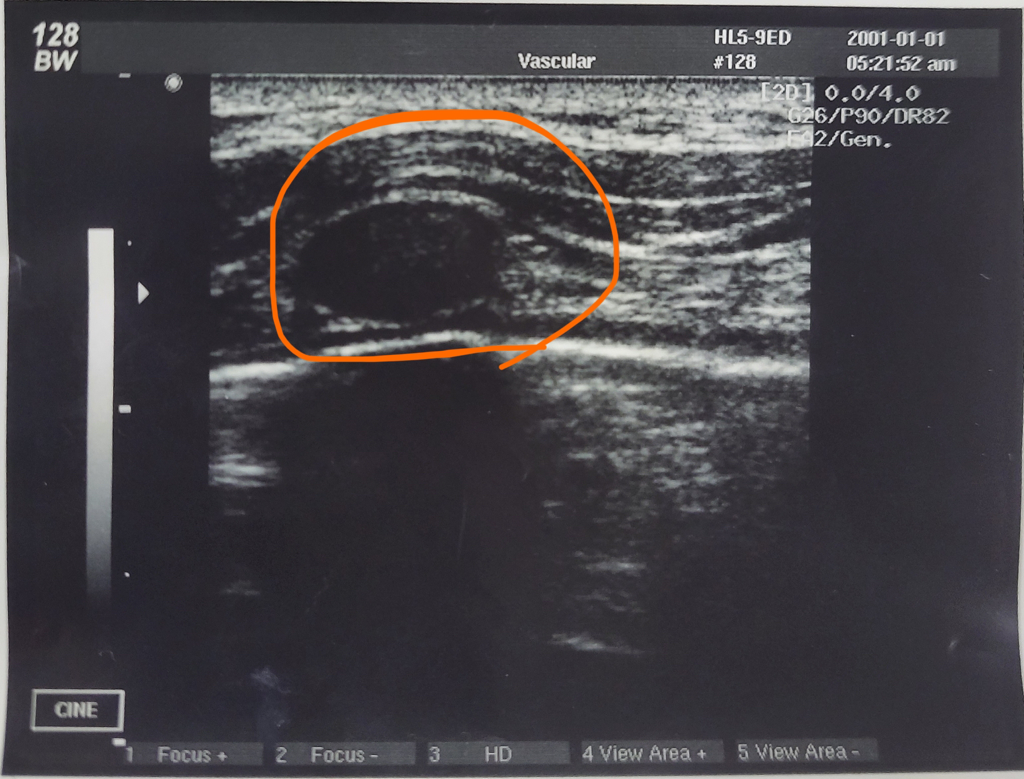

남자 유방 쪽 Cyst 같은게 보여요 cyst 맞나요??

대학교 실습시간에 초음파 실습을 했는데 같은반 형이 유방쪽에 물주머니 같은게 보여서 갈비뼈인지 물주머니인지 궁금해서 질문 드립니다!!

초음파에 보이는 혹같은 부분은 가슴의 갈비뼈로 보입니다. 초음파는 뼈를 통과하지 못하기 때문에 뒤쪽으로 검은 음영(그림자)이 보이게 됩니다.